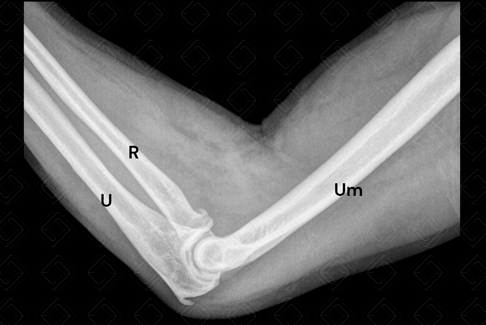

Texto alternativo para a imagem Radiografia de cotovelo, estudo em perfil. Créditos: Athena Hub/Medical Harbour

Legenda das siglas: R = rádio; U = ulna; Um = úmero.